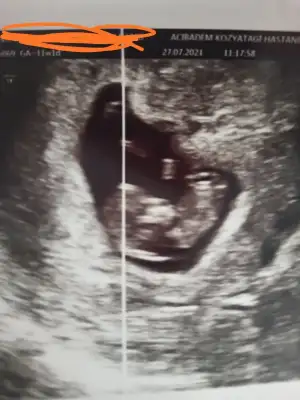

10 haftaya göre kız ama en iyi 11 12 13 haftalar olmalı tekrar USG paylasin6haftalik 10 ve 11haftalik görüntüsü

Ne için erkek dediniz bebeğin yönü için mi?Şimdilik erkek yönünde ama en iyi 11 12 13 haftalar olmalı tekrar USG paylasin

Teşekkürler canım 11 haftalık olanı hep erkek yorum yapıldı. Nasıl anlaşılıyor acaba ben hiç anlamıyorum10 haftaya göre kız ama en iyi 11 12 13 haftalar olmalı tekrar USG paylasin![]()

Bunun nubu görünmüyor o görünen kordonu11hafta

Teşekkürler yorumunuz içinBunun nubu görünmüyor o görünen kordonu